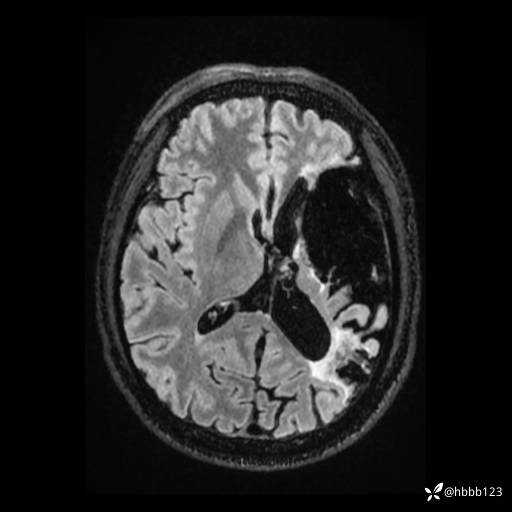

T2 Flair: